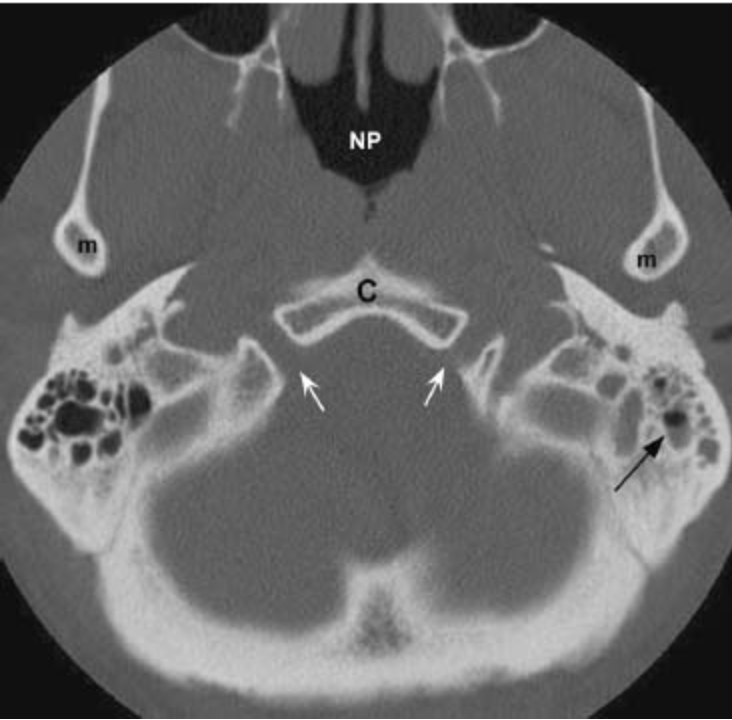

Pterygopalatine Fossa

• Should think of pterygopalatine fossa as one of the major intersections of the face/skull

The following pictures are a fantastic way to visualize the borders rather than just memorizing them which is a sure fire way to forget them by tomorrow.

• Anterior & Superior - communicates with inferior orbital fissure

• Inferior - Greater & lesser palatine canals

• Communicates with palate

• Lateral - Pterygomaxillary fissure

• Communicates with masticator space

• Medial communication - Sphenopalatine foramen & Palatine bone

• Communicates with nasal cavity

• Transmits

• Sphenopalatine artery

• Posterior superior nasal nerves & nasopalatine nerve

• Posterior

• Posterior-medial - Palatovaginal canal

• Communicates with nasopharynx

• Transmits pharyngeal nerve and pharyngeal branch of maxillary artery

• Posterior-superior - Foramen rotundum

• communicates with Meckel cave & Cavernous sinus

• Posterior-inferior - pterygoid canal (aka vidian canal)

• Communicates with middle cranial fossa

• Transmits vidian nerve, artery and vein